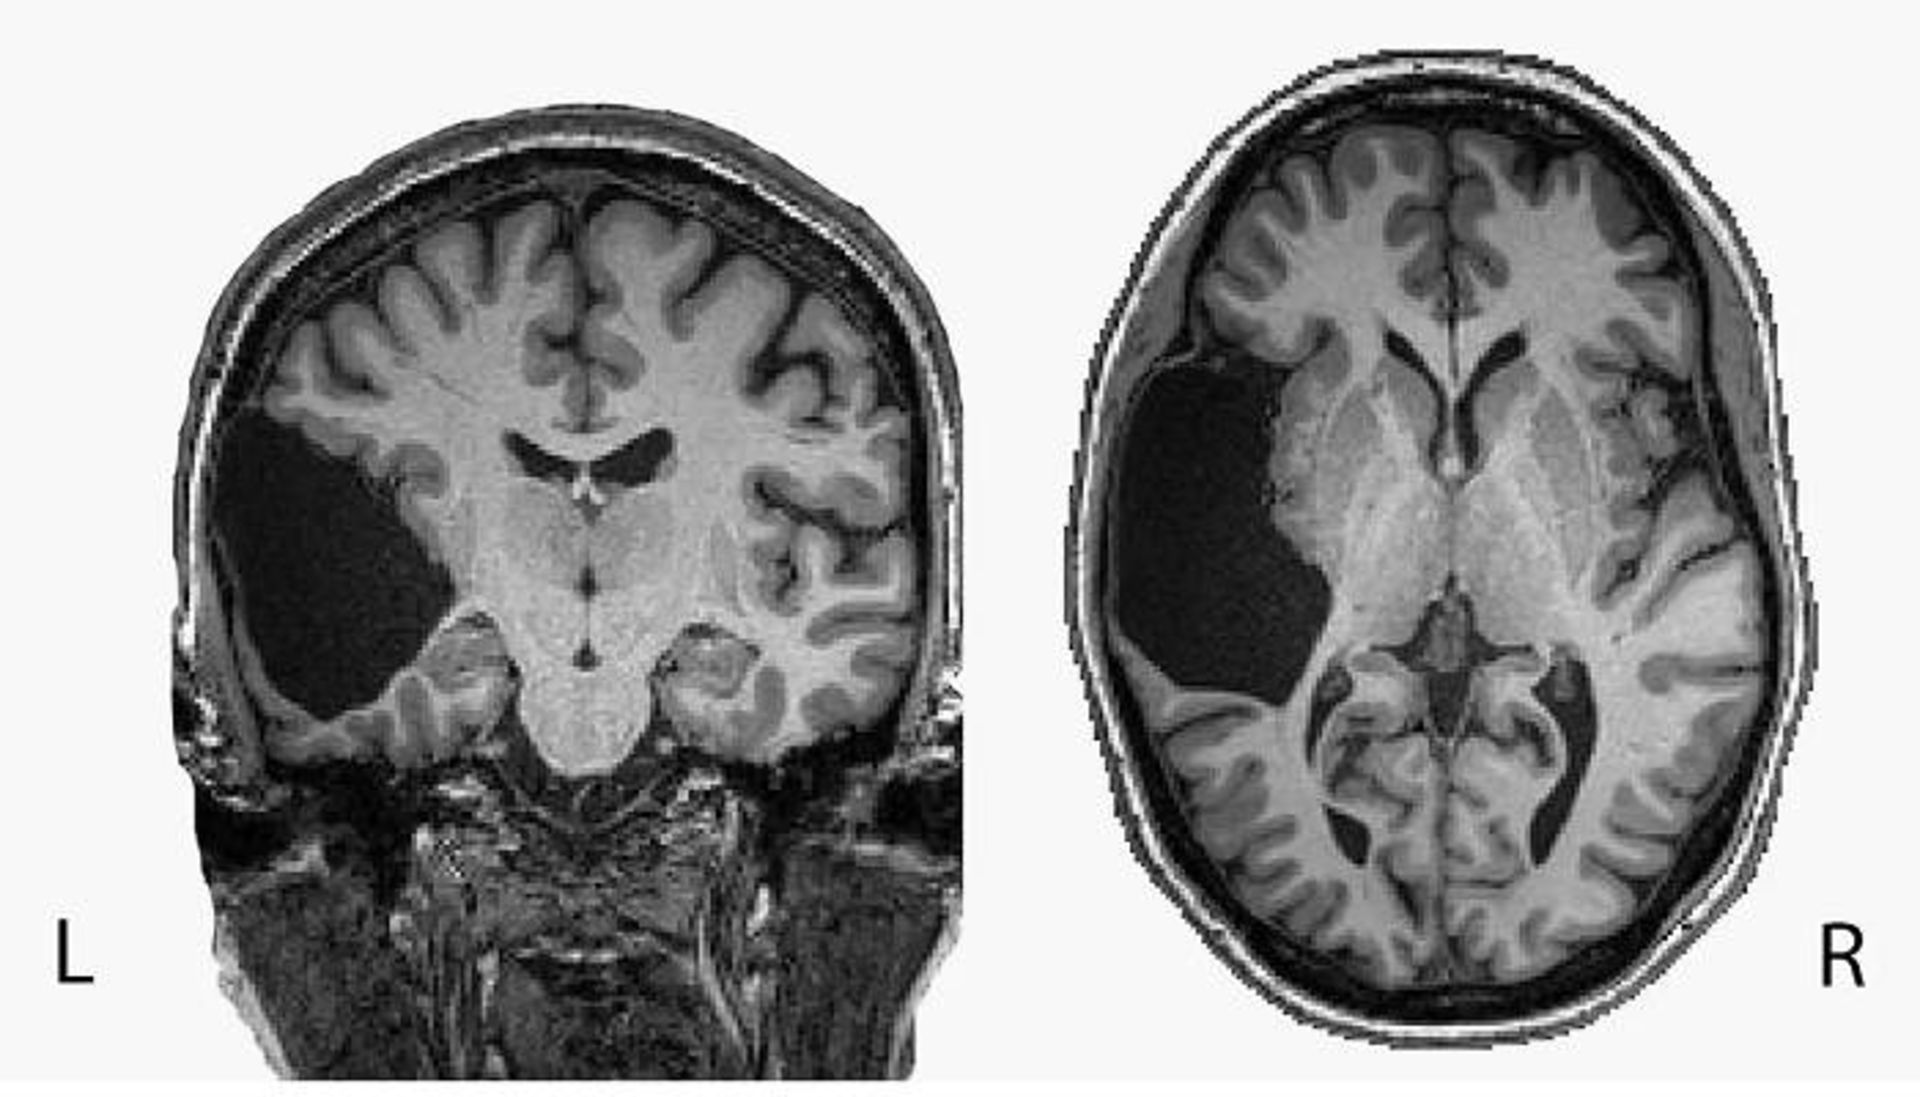

اسکن مغز ای جی / brain scan

تصویر MRI از مغز ای‌جی